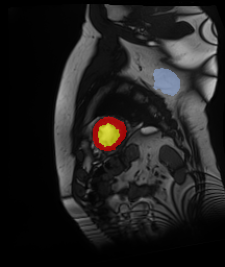

Medical data often exhibits long-tail distributions with heavy class imbalance, which naturally leads to difficulty in classifying the minority classes (i.e., boundary regions or rare objects). Recent work has significantly improved semi-supervised medical image segmentation in long-tailed scenarios by equipping them with unsupervised contrastive criteria. However, it remains unclear how well they will perform in the labeled portion of data where class distribution is also highly imbalanced. In this work, we present ACTION++, an improved contrastive learning framework with adaptive anatomical contrast for semi-supervised medical segmentation. Specifically, we propose an adaptive supervised contrastive loss, where we first compute the optimal locations of class centers uniformly distributed on the embedding space (i.e., off-line), and then perform online contrastive matching training by encouraging different class features to adaptively match these distinct and uniformly distributed class centers. Moreover, we argue that blindly adopting a constant temperature $\tau$ in the contrastive loss on long-tailed medical data is not optimal, and propose to use a dynamic $\tau$ via a simple cosine schedule to yield better separation between majority and minority classes. Empirically, we evaluate ACTION++ on ACDC and LA benchmarks and show that it achieves state-of-the-art across two semi-supervised settings. Theoretically, we analyze the performance of adaptive anatomical contrast and confirm its superiority in label efficiency.

翻译:医学数据经常呈现长尾分布和重度类别不平衡,这自然导致在对少数类别(即边界区域或罕见目标)进行分类时出现困难。最近的研究在长尾情况下通过装备医学影像的无监督对比标准,明显改进了半监督医学图像分割。然而,在标记的数据部分中,类别分布也极为不平衡,因此它们的表现如何仍不清楚。在本研究中,我们介绍一种采用自适应解剖对比度改进的对半监督医学分割行动的框架(ACTION++)。具体来说,我们提出了一种自适应监督对比损失,它首先在嵌入空间上计算出不同类别的优化位置(即离线),然后通过鼓励不同类别之间的特征与这些不同和均匀分布的类别中心相适应的在线对比匹配训练来进行自适应匹配。此外,我们认为,在长尾医疗数据中盲目采用常温度$\tau$不是最优的,因此通过一个简单的余弦计划来使用动态$\tau$来产生更好的多数类别和少数类别之间的分离。在实证方面,我们在ACDC和LA基准测试中评估ACTION++,并展示了其在两种半监督设置下的最新成果。从理论上讲,我们分析了自适应解剖对比度的性能,并证实了它在标签效率上的优越性。